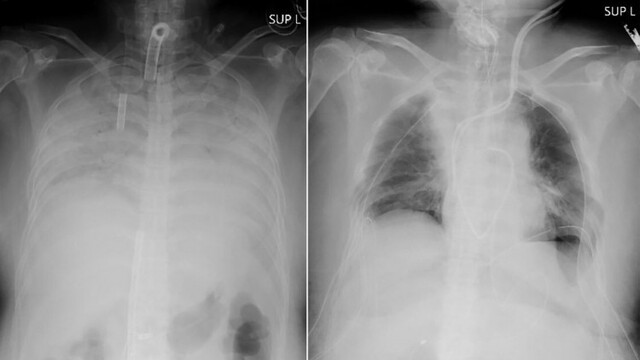

Žena sa nakazila koronavírusom koncom minulého roka a vyvinuli sa u nej ťažkosti s dýchaním, ktoré sa rýchlo zhoršovali. V inej nemocnici ju napojili na prístroj udržiavajúci život, ktorý vyše tri mesiace pracoval ako umelé pľúca. Žena mala v tom čase svoje pľúca už ťažko poškodené. A hoci neskôr už nemala v tele koronavírus, jej pľúca nefungovali a neboli ani liečiteľné. Jedinou jej šancou, aby žila, bolo prijať pľúcny transplantát, vysvetlila univerzita.

Jej manžel a syn dobrovoľne darovali časti svojich pľúc a operáciu urobil na univerzite v Kjóte 30-členný tím vedený doktorom Datem. Manžel venoval časť ľavej strany pľúc a syn daroval časť pravej strany pľúc. Žena podľa očakávania opustí nemocnicu do približne dvoch mesiacov a k normálnemu životu sa vráti do troch mesiacov, doplnila nemocnica.